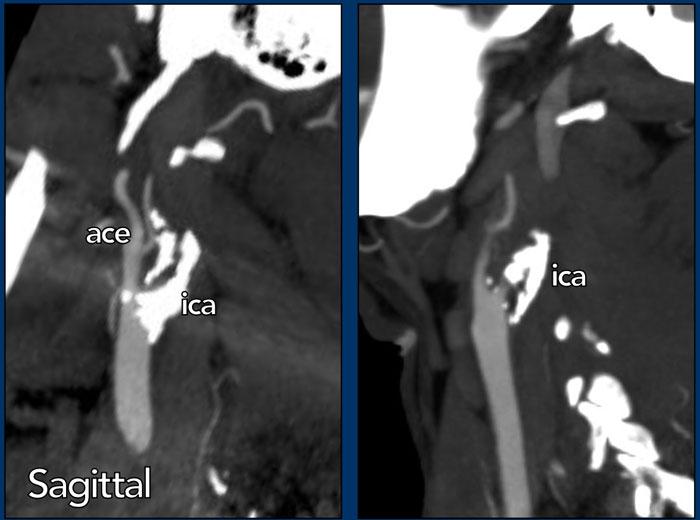

Tắc Nghẽn Giả

Tắc nghẽn giả động mạch cảnh trong đoạn cổ là tình trạng tắc nghẽn đơn độc của động mạch cảnh trong (ICA) đoạn nội sọ xa, bắt chước hình ảnh tắc nghẽn ICA ngoài sọ trên CTA hoặc DSA.

Trong tắc nghẽn giả, hình ảnh trông như thể có tắc hoàn toàn tại ICA ngay trên mức xoang cảnh.

Thuốc cản quang đi vào ICA gặp khó khăn khi di chuyển lên phía trên do máu ứ đọng trong lòng ICA, vì ICA không có các nhánh bên lớn.

Thuốc cản quang chỉ thấm chậm vào cột máu ứ đọng này, tạo ra hình ảnh loang màu nước.

Trên CTA, có thể thấy tỷ trọng thuốc cản quang giảm dần trong ICA với hình ảnh loang màu nước.

Vấn đề cốt lõi là tắc nghẽn dòng chảy ra tại mức đỉnh chữ T động mạch cảnh.

Hai trường hợp tắc nghẽn giả động mạch cảnh.

Trong trường hợp đầu tiên (bên trái), thuốc cản quang dừng khá đột ngột, mặc dù có thể thấy một vùng nhỏ với tỷ trọng thuốc giảm dần.

Trong trường hợp này, việc phân biệt giữa tắc nghẽn giả với lóc tách thành mạch hoặc tắc nghẽn do xơ vữa có thể khó khăn.

Tuy nhiên, chúng ta không thấy hình dạng ngọn lửa điển hình của xoang cảnh như trong lóc tách thành mạch, và không có dấu hiệu xơ vữa động mạch (không có mảng xơ vữa hay vôi hóa).

Trong trường hợp thứ hai, tỷ trọng thuốc cản quang giảm dần rõ ràng trên một đoạn dài hơn (đầu mũi tên).

Đây rõ ràng là tắc nghẽn giả động mạch cảnh.